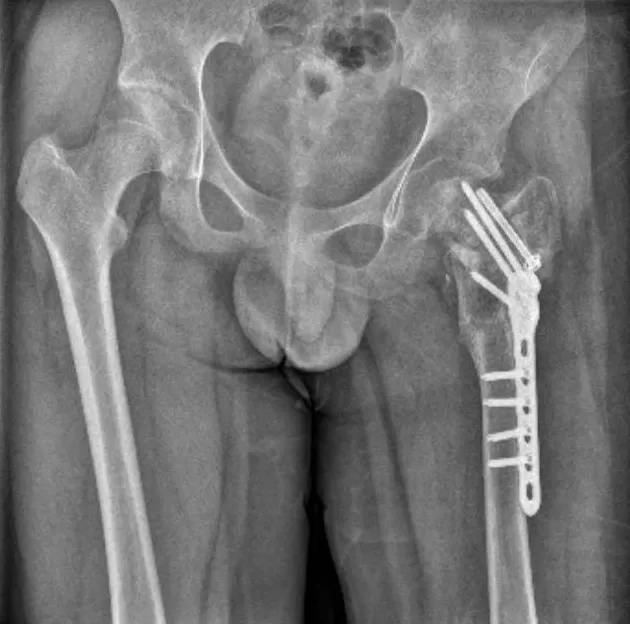

耽误10天,小武错过了最佳治疗时机。9月9日被妈妈送到泉州市正骨医院,他已是陈旧性骨折。医生说,“刚摔时只是骨裂,如果立刻来医院处理,休息一两个月就好了。”

2023年11月13日出院,小武的诊断结论列出左股骨颈陈旧性骨折、左髋部感染、肺部感染等十余种症状。

▲小武左腿骨折

武女士说,事发两年来,小武共做了六次手术,仅左髋部感染就做了四次手术,但损坏部分依然长不出来。如今,小武骨骼萎缩,拄双拐走路时一瘸一拐,成了“长短腿、粗细腿”。

医生说,小武股骨头坏死已到晚期,只能做康复治疗。他的学业也已荒废两年多。医生还说,后期可能要把胯骨和髋骨置换成人工骨骼。但昂贵的医疗费谁来出,至今没有答案。